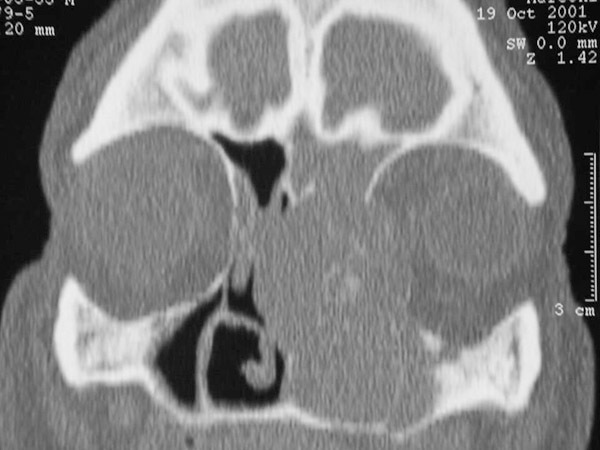

Coupe scannographique coronale montrant une tumeur ethmoïdale gauche invasive, lysant les parois médiale et latérale. Cet aspect agressif est fortement évocateur d’un adénocarcinome de l’ethmoïde. Ces tumeurs restent latentes très longtemps et sont souvent diagnostiquées à un stade tardif. Elles doivent être évoquées et recherchées devant toute sinusite rebelle au traitement, notamment si le patient rapporte des épisodes d’épistaxis récidivants toujours du même côté.